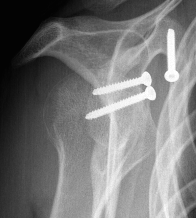

Case 1

- displaced glenoid fracture and neck fracture

- ORIF both through posterior / Judet approach